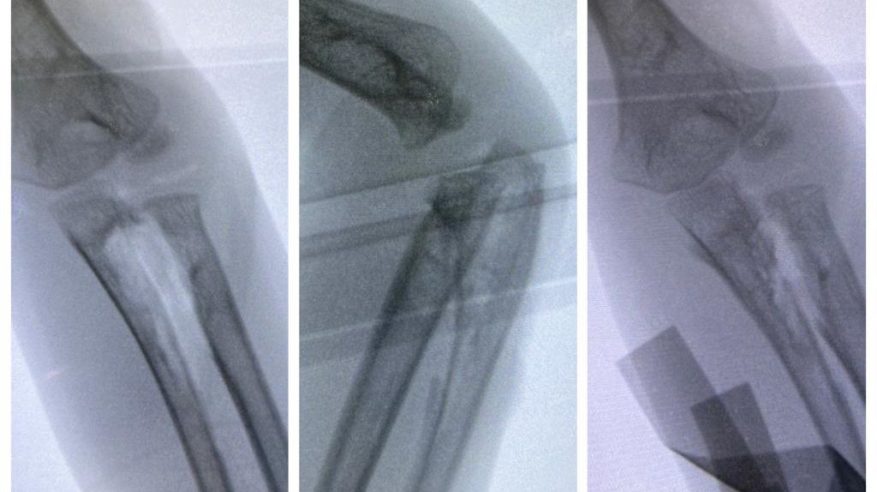

نجح فريق طبي متخصص بجراحة المفاصل والعظام في مستشفى الولادة والأطفال ببريدة بإنهاء معاناة طفل يبلغ من العمر أربعة أعوام كان يشكو من عدم المقدرة على تحريك عظام الساعد الأيسر منذ ولادته.

وأوضح تجمع القصيم الصحي أن عيادة جراحة العظام للأطفال في المستشفى استقبلت الطفل برفقة ذويه، وبعد القيام بعمل المعاينة السريرية وإجراء الفحوصات والأشعة المقطعية اللازمة تبين أن الطفل مصاب بالتحام خلقي في عظام الساعد الأيسر، مما جعله يفقد الحركة الدورانية المعتادة للساعد بشكل تام.

جراحة دقيقة

وبين أن المستشفى أجرى العمل الجراحي اللازم للطفل وذلك باستئصال الجزء الزائد غير الطبيعي الذي يصل بين العظمين، كما تم وضع مادة وأنسجة فاصلة بين العظمين لتجنب حدوث الالتحام، وقد تم التأكد سريرياً من عودة الحركة للساعد بشكل كامل عقب الانتهاء من العمل الجراحي، بالإضافة إلى إجراء التصوير الشعاعي أثناء تنفيذ العملية بنجاح، ليغادر الطفل بعدها المستشفى برفقة ذويه مصحوباً بالعافية.